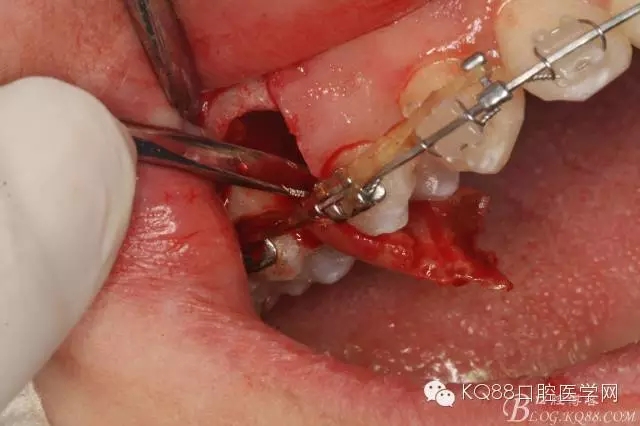

圖13. 用小球鉆去除約1mm牙槽骨,暴露15牙根面約5mm。

圖14.用小球鉆縱分15牙根